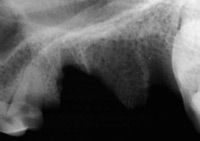

Q: How should I treat dentigerous cysts?